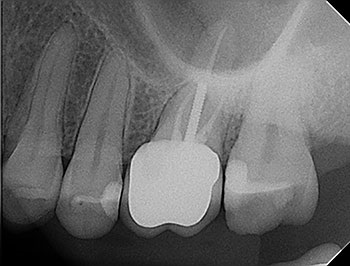

Fig. 1: Preoperative PA.

Case 1:A J-shaped lesion

Tooth #30 had a diagnosis of previous root canal treatment with symptomatic apical periodontitis. The mesial root had a classic J-shaped radiographic lesion and a narrow probing defect from the buccal furcation to the root apex. No crack could be seen on what little root surface was visible. The likelihood of VRF, or the possibility of a failing root canal with a chronic apical abscess, were discussed. The latter could be treatable. The plan was to attempt re-treatment after internal inspection for a possible VRF.